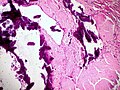

Image